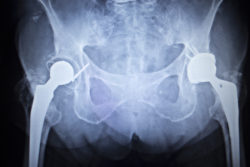

X-ray scan image of hip joints with orthopedic hip joint replacement implant head and screws in human skeleton in blue gray tones. Scanned in orthopedics traumatology surgery hospital clinic.Another Styker Accolade lawsuit is filed against Howmedica Osteonics Corp. by a man alleging severe adverse effects due to the Stryker hip implant device.